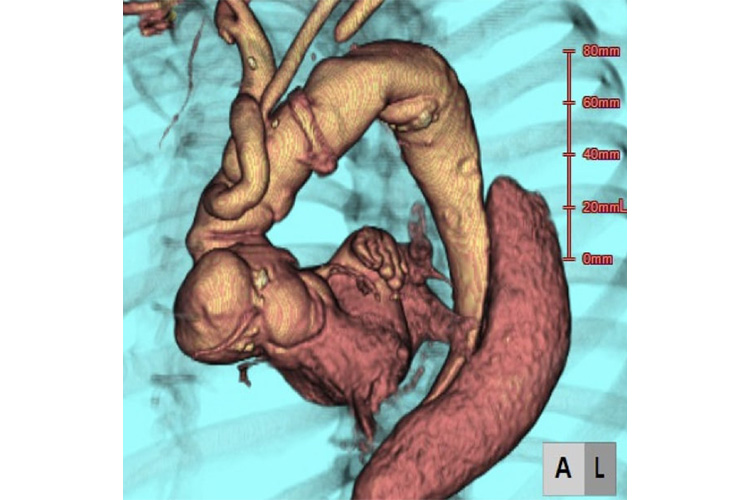

④造影CT検査

造影CT検査のイメージ

造影剤を併用しCTをとることで、大動脈解離の有無を診断します。Stanford A型かB型か、他の動脈が閉塞していないか、心タンポナーデに至っていないかなど評価します。